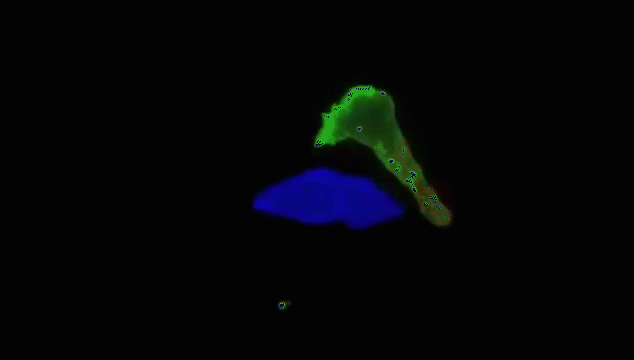

当T细胞(绿)发现癌细胞(蓝)时,通过分泌的毒素附着在癌细胞上,来检测、分辨正常细胞与癌细胞。

查明之后,T细胞(红)连接癌细胞(蓝),打破癌细胞外壁,向其表面引入毒性蛋白。

一旦细胞毒素(红)进入,癌细胞会逐渐衰弱、死亡。而T细胞(绿)继续在人体内巡逻,寻找下一个目标。